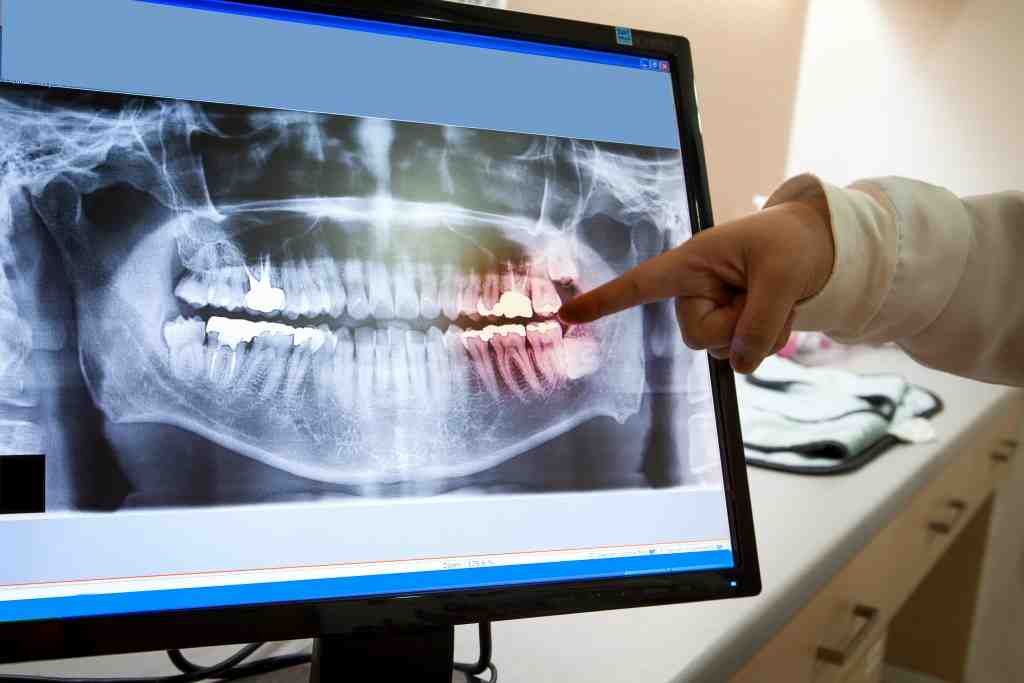

How to identify dental implants by x ray Dental News Network How To Identify An Implant learn to characterize and identify dental implants from radiographs using a free online database and consultation service. spotimplant helps you identify any unknown dental implant from a radiograph using artificial intelligence. insider tips to make implant identification more accurate and successful on whatimplantisthat.com: when you’re trying to identify a specific dental implant, it can be helpful. How To Identify An Implant.

How to identify dental implants by x ray Dental News Network How To Identify An Implant spotimplant is the most comprehensive dental implant database with thousands of brands, models and catalogs. Most people look at things differently, so it is important to find a common denominator and build on that. learn how to identify unknown dental implants using radiographs, online databases, and implant identification services. learn to characterize and identify dental implants from. How To Identify An Implant.

How to identify dental implants Dental News Network How To Identify An Implant spotimplant helps you identify any unknown dental implant from a radiograph using artificial intelligence. when you’re trying to identify a specific dental implant, it can be helpful to refer to the history of implants. insider tips to make implant identification more accurate and successful on whatimplantisthat.com: Most people look at things differently, so it is important to. How To Identify An Implant.

How to identify dental implants by x ray Dental News Network How To Identify An Implant spotimplant helps you identify any unknown dental implant from a radiograph using artificial intelligence. Most people look at things differently, so it is important to find a common denominator and build on that. insider tips to make implant identification more accurate and successful on whatimplantisthat.com: spotimplant is the most comprehensive dental implant database with thousands of brands,. How To Identify An Implant.

How to identify dental implants by x ray Dental News Network How To Identify An Implant learn to characterize and identify dental implants from radiographs using a free online database and consultation service. learn how to identify unknown dental implants using radiographs, online databases, and implant identification services. Most people look at things differently, so it is important to find a common denominator and build on that. spotimplant is the most comprehensive dental. How To Identify An Implant.

How to identify dental implants Dental News Network How To Identify An Implant Spotimplant.com also offers an artificial. Most people look at things differently, so it is important to find a common denominator and build on that. spotimplant helps you identify any unknown dental implant from a radiograph using artificial intelligence. learn how to identify unknown dental implants using radiographs, online databases, and implant identification services. spotimplant is the most. How To Identify An Implant.